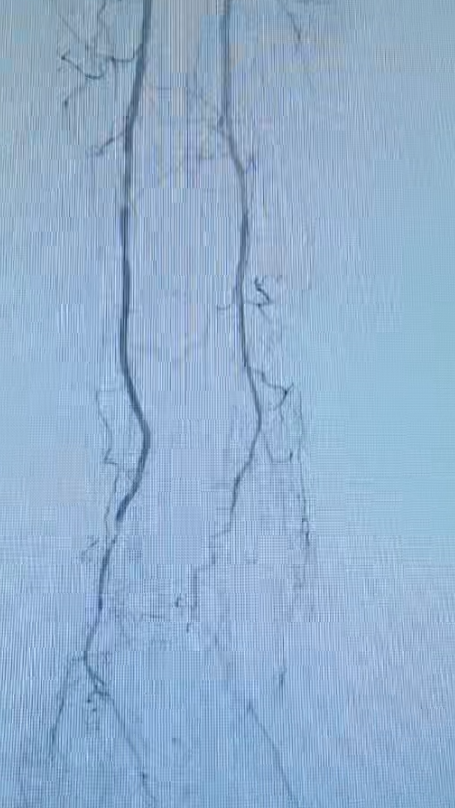

IVUS引导下的准分子激光斑块消蚀术中影像

随后,团队启动“准分子激光斑块消蚀系统”。在IVUS明确病变性质后,激光导管被精准送达目标位置。它发射特定波长的脉冲激光,能以“微观爆破”方式高效、安全地将硬化斑块甚至顽固钙化组织气化消蚀为微小微粒,从而为后续治疗开辟出通畅通道,这一技术尤其适用于导丝虽能通过但球囊无法扩张的坚硬病变。

手术中,血管外科团队首先将纤细的IVUS导管送入血管闭塞段。IVUS如同深入血管内部的“高清雷达”,实时生成血管横截面的高清图像,清晰显示闭塞长度、斑块性质及血管真腔位置,为术者规划个体化治疗路径提供了精准依据。